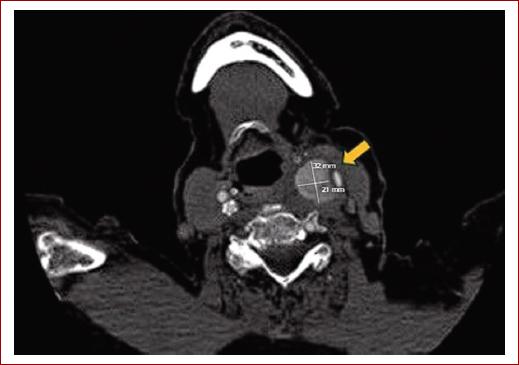

Ante un síndrome de Horner izquierdo con una masa cervical pulsátil, se sospechó de patología carotídea como primera alternativa diagnóstica. Con estos datos, se solicitó una angio-TC donde se observaba una masa hipercaptante a nivel de la bifurcación carotídea izquierda de 32 x 21 milímetros. Esta masa comprimía y desplazaba las estructuras vasculares lateralmente (Figs. 1 y 2).

Figura 2 Corte axial de angiografía computarizada donde se observa masa hipercaptante en eje carotídeo izquierdo de 30 x 21 milímetros (flecha amarilla).